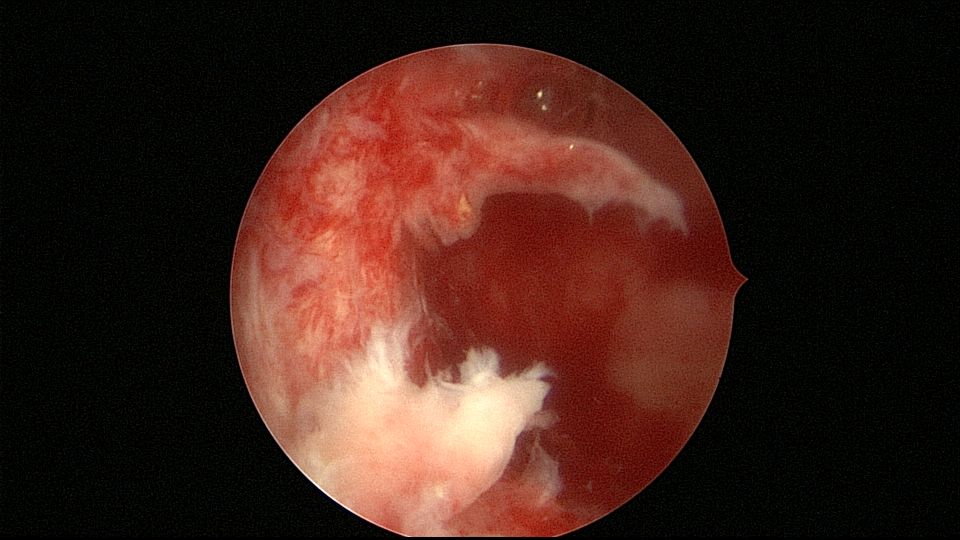

患者68岁,G3P1,顺产1次,安环42年,绝经20年,外院取环失败。子宫后位,宫颈及子宫萎缩,距宫颈内口1cm以上宫颈管封闭致密粘连,B超监护下异物钳分离粘连,打开进入宫腔的通道,艰难扩宫至6号扩宫棒,见O型环与两侧宫壁崁顿,异物钳无法取出,取环钩将环拉至宫颈外口,中弯钳牵拉,完整取出节育环,环变形,很艰难的取环经历。